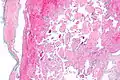

Intravascular papillary endothelial hyperplasia is a rare, benign tumor. It may mimic an angiosarcoma, with lesions that are red or purplish 5-mm to 5-cm papules and deep nodules on the head, neck, or upper extremities.[1][2]: 592

Histopathology Images